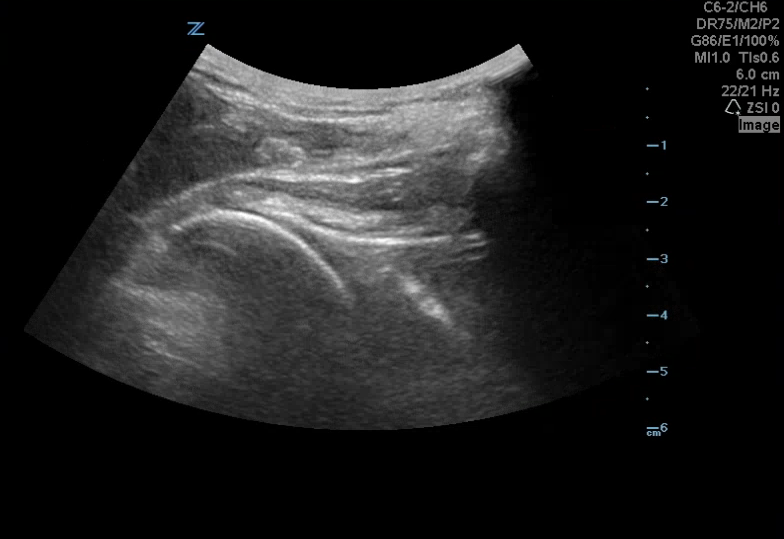

A 42 yoM presented to the ED with a left shoulder dislocation. The ultrasound team looked at his dislocated shoulder (Image 1) and gave an Intraarticular lidocaine injection. The providers reduced his shoulder and then looked for confirmation using ultrasound (Image 2).

Take your linear or curvilinear probe and place it in transverse orientation on the patient’s back next to the humerus (image 3). The glenoid should articulate directly with the humeral head (image 4). In an anterior shoulder dislocation, the humeral head will be deeper on your screen because it is further from the probe. In a posterior shoulder dislocation, the humeral head will appear more superficial because it is closer to your probe (image 5).